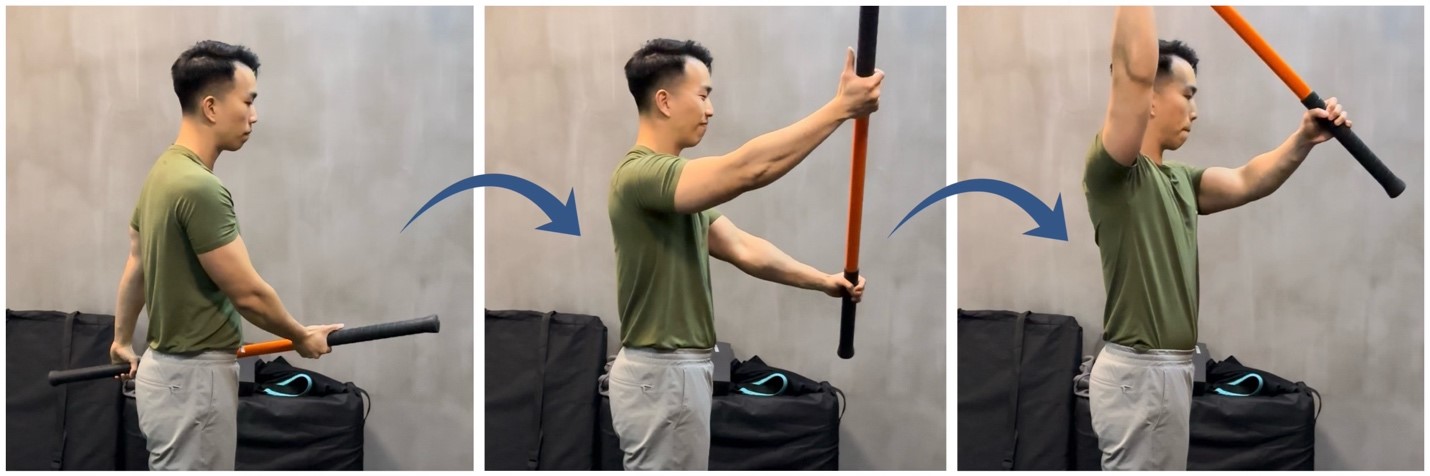

運動示例:輔助型肩關節屈曲 (Assisted Range of Motion Shoulder Flexion)

階段3 – 漸進式增強力量 (受傷後8-12週)